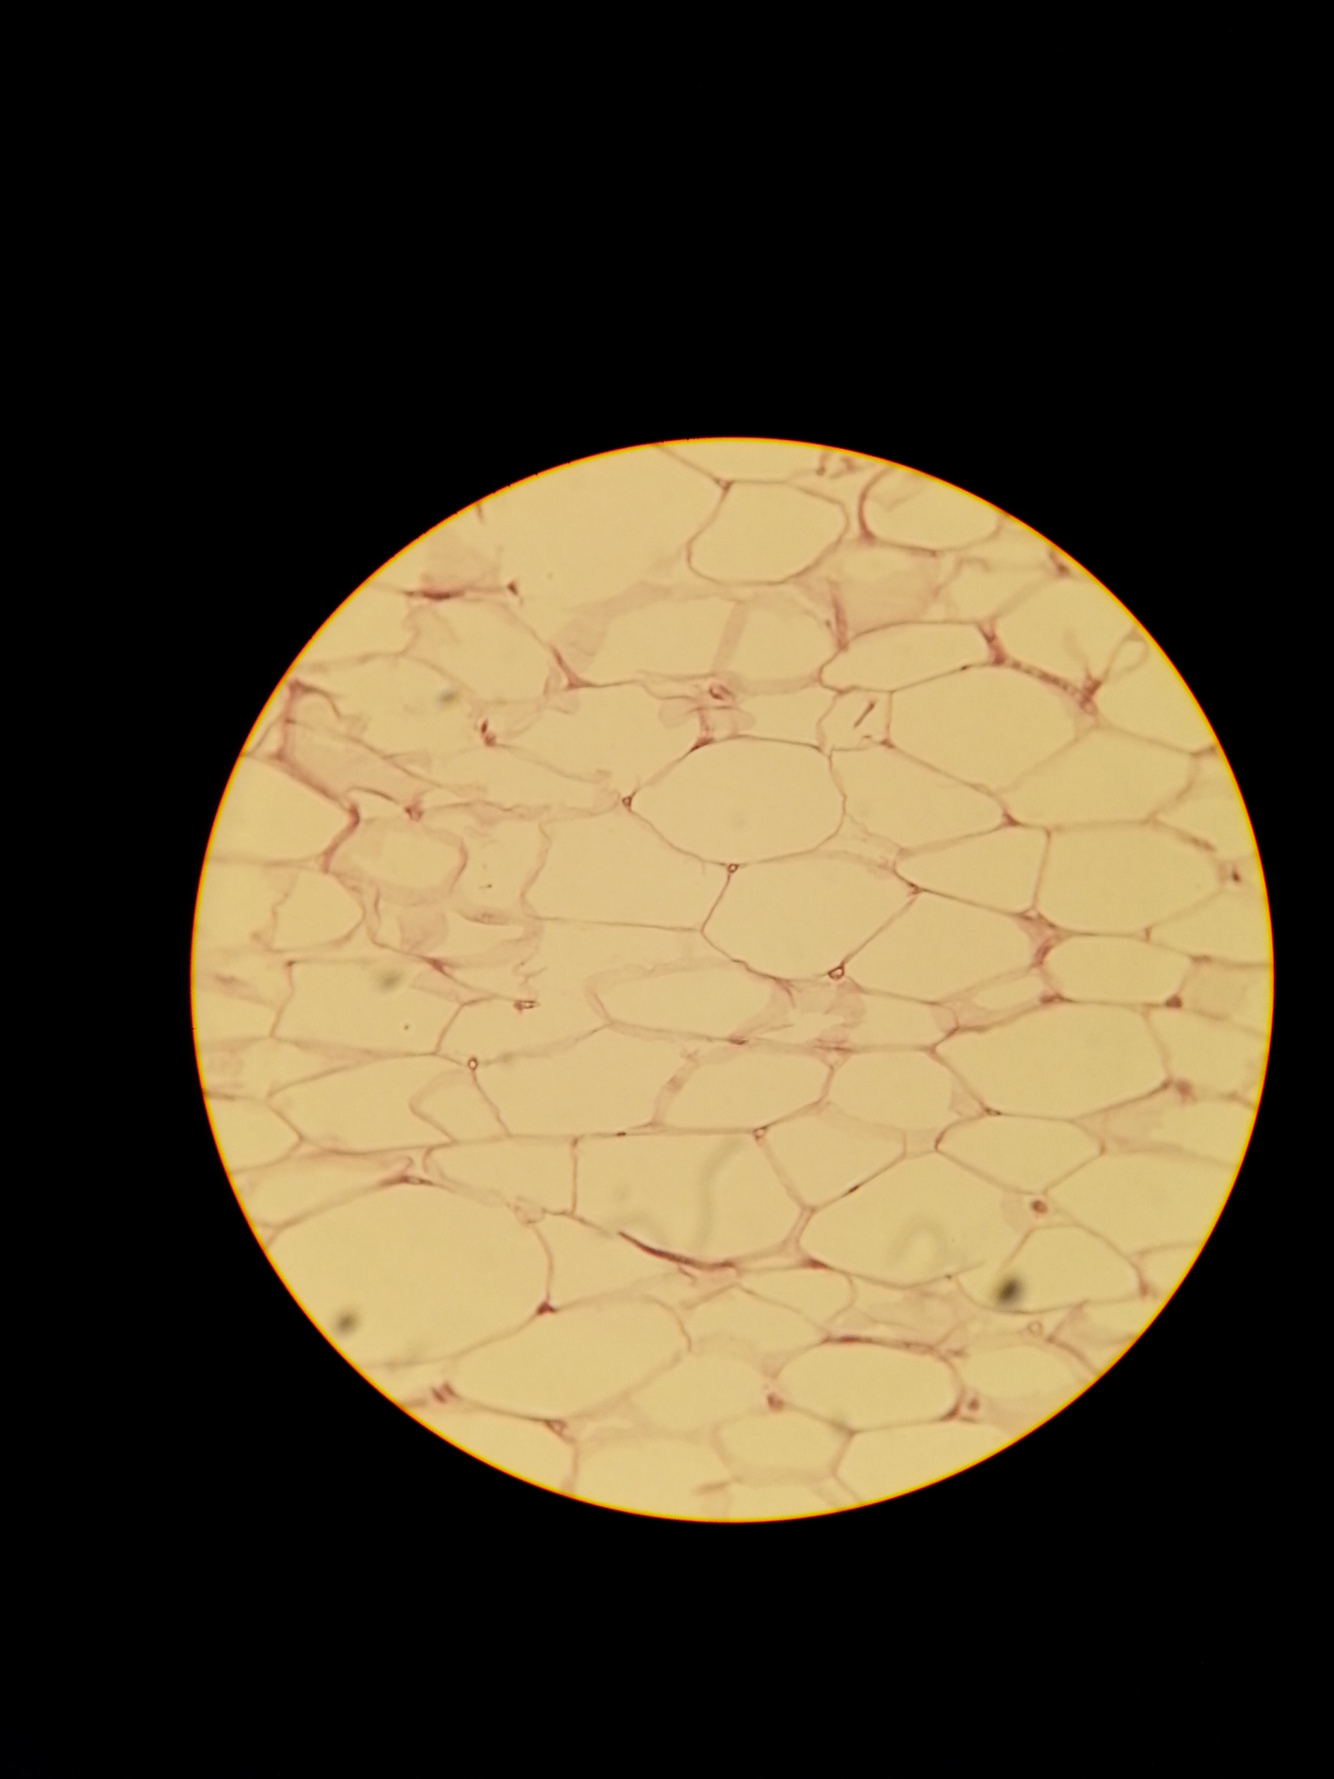

What type of tissue is this? Name a location and function.

Adipose Connective Tissue

Location: Subcutaneous layer; breasts, kidneys, eyeballs

Function: Long-term energy stroage, protection, insulation